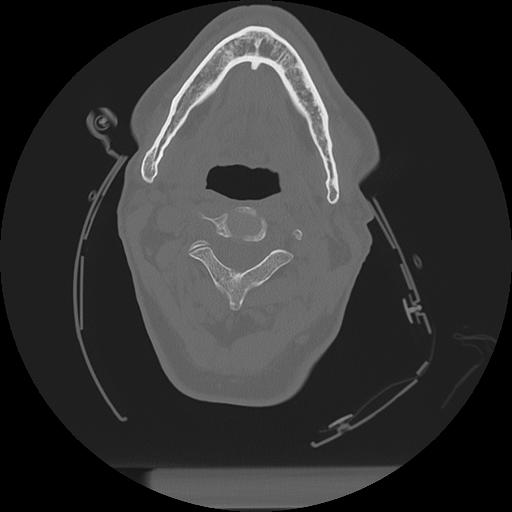

11 HUESO,,Axial,2.0,HUESO,,